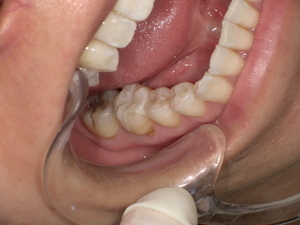

治療前の状態:古い被せ物が健康と審美性を損なう

診察の結果、下奥歯に装着されていた金属の被せ物は歯にしっかり適合しておらず、隙間から 虫歯が再発 していました。さらに別の歯の詰め物も劣化しており、口腔内全体でリスクが高い状態です。

Before

- 古い被せ物は色と形が不自然

- 歯茎との境目に虫歯が再発